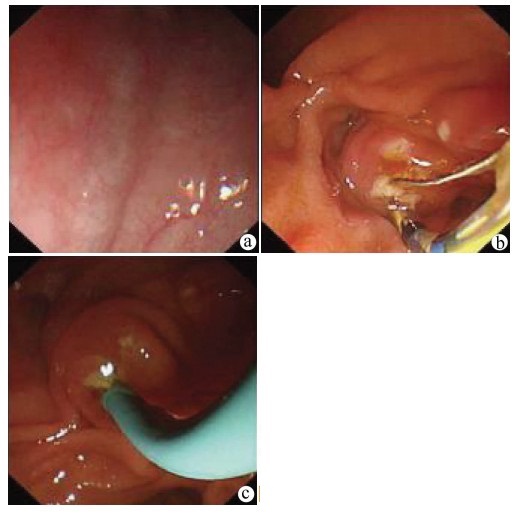

肝硬化失代偿期合并恶性胸膜间皮瘤并腹膜转移1例报告

卢利霞, 谢小青, 郑英, 刘鑫, 王建平, 王俊科, 王盼, 于晓辉

2022, 38(2): 418-419. DOI: 10.3969/j.issn.1001-5256.2022.02.030

摘要(913) HTML (261) PDF (2461KB)(58)

摘要: